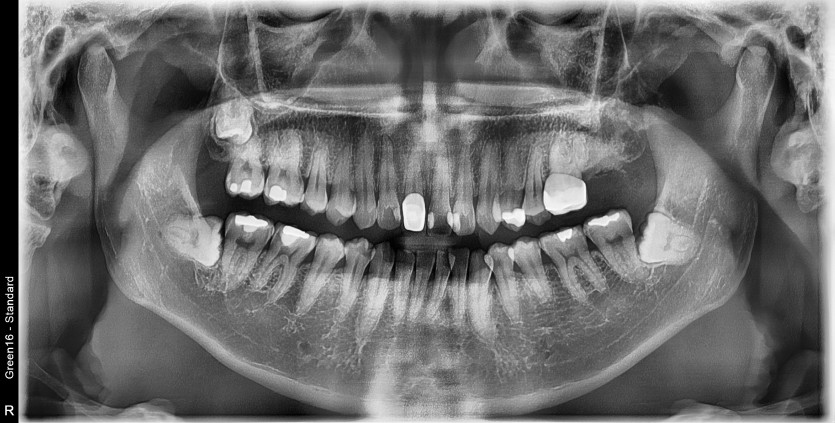

#28 사랑니 발치(#27포함)

#28 사랑니 발치(#27 포함)

구강 외과 전문의가 당일 발치했습니다.